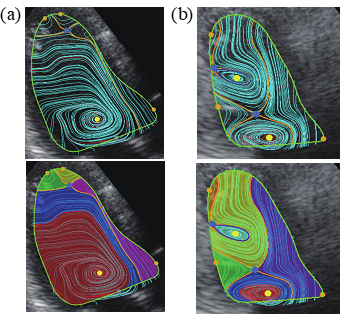

図2(a)健常な心臓の心エコーVFMデータ とTFD解析で得られた渦流領域(赤)

(b) 心不全患者の心臓の心エコーVFMデータとTFD解析で得られた渦流領域(赤と水色)

※画像は超音波画像血流解析ソフトiTEcho®(研究用)で作成した物です

この研究成果を通じて、これまで非常に重要な役割を果たしていると信じられていながらも明確に捉えられなかった心臓血流内の「渦流」が曖昧さなく同定され、また渦を支える血流の構造が余すところなく解明され、長年人類の神秘とされてきた渦流の役割やメカニズムが明確になり、医学生理学分野での基礎研究として意義が生まれてくるであろうと考えます。また心疾患の診療においても、例えば健常例と比べて心不全例ではどのように渦が分離し崩れていくのかなどが目で見ても明らかになり、また、質的な差として数学的に表現され、心不全などの心疾患ではなぜ血流の拍出効率が悪くなるのかといった病態自体の解明が期待されます。